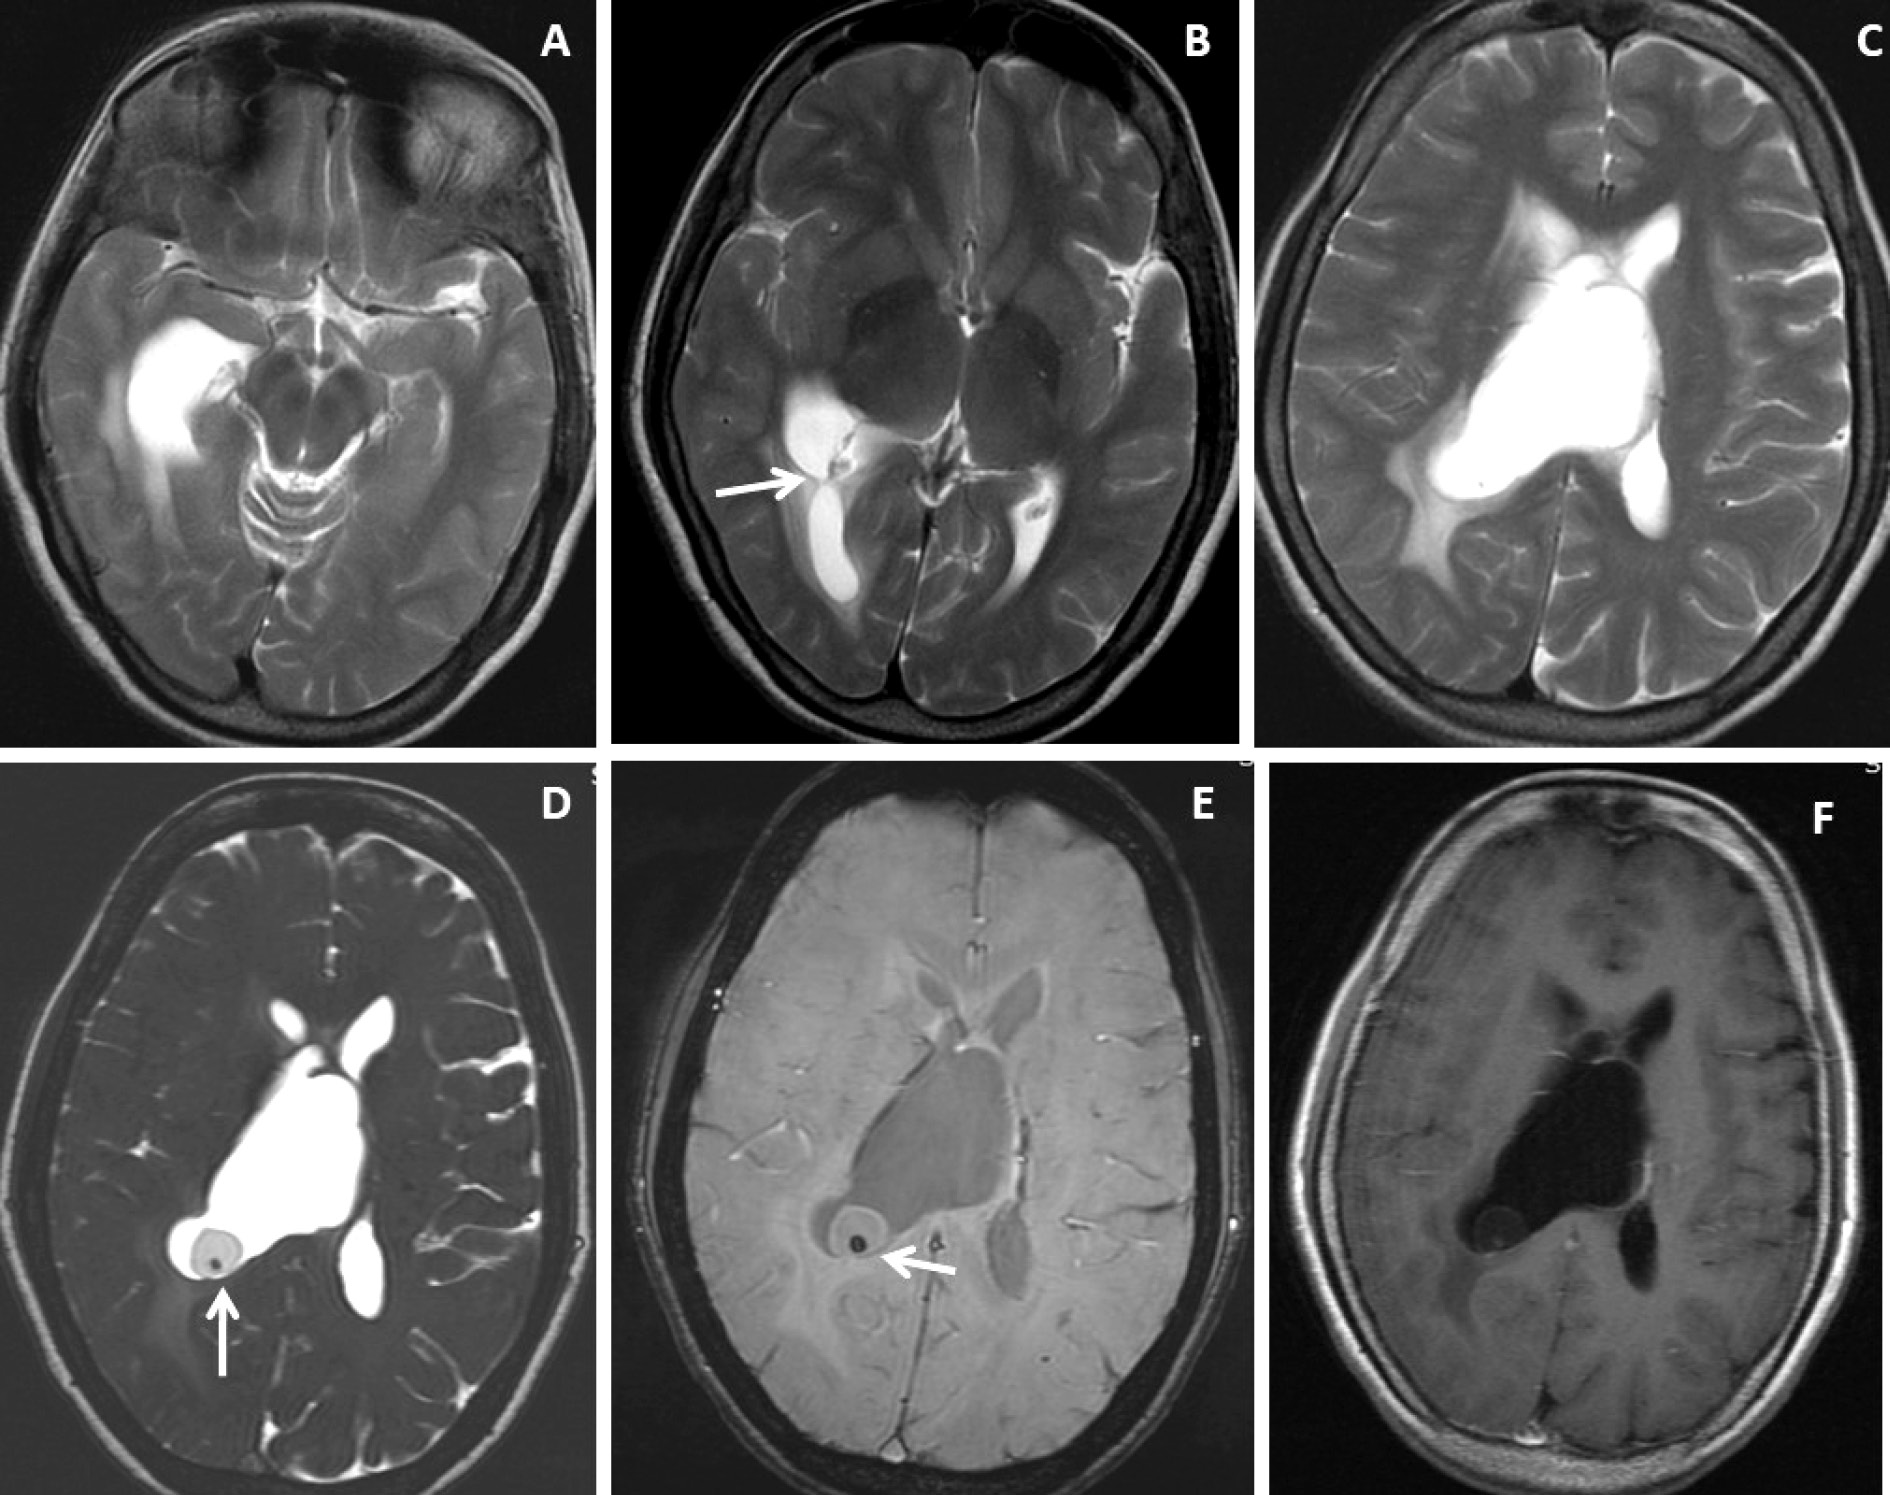

Figure 1. Brain magnetic resonance imaging of 52 years female with headache and vomiting. (A-C) Axial T2WI images show asymmetrical hydrocephalus with entrapment of temporal horn of the right lateral ventricle with narrowing / adhesion in the trigone of the lateral ventricle (arrow) with surrounding periventricular CSF seepage. (D) Heavily T2-weighted image shows an intraventricular neurocysticercus lesion with a T2 hypointense scolex within (arrow). (E) Axial susceptibility-weighted image shows nodular blooming of the calcified scolex within the thin wall IVNCC (arrow). (F) Axial post-gadolinium T1W image shows thin smooth peripheral cyst wall enhancement with the smooth ependymal enhancement of the asymmetrically dilated lateral ventricle.

Very thin smooth cyst wall enhancement was observed in 9(90%) patients (Figure 1 and 2) and irregular peripheral rim-like wall enhancement with an irregular nodule in 1(10%) patient. Ventricular ependymitis with smooth to irregular ependymal lining enhancement was observed in 7(70%) patients (Figure 3). Presence of hydrocephalus detected in 8(80%), where MRI revealed asymmetrical enlargement of lateral ventricle with periventricular CSF seepage in 4(40%) patients (Figure 1), dilatation of 3rd ventricle in 2(20%) patients and ballooned 4th ventricle in another 2(20%) patients(Figure 4).

T2WI, DRIVE and SWI visibility score of the scolex of intraventricular neurocysticercosis (IVNCC): In 10patients with intraventricular neurocysticercosis, the scolex was distinctly visualized (visibility score 2) in 2(20%) patients on T2WI, 8(80%)patientson 3D-DRIVE (Figure 1) and 3(30%) on SWI sequence (Figure 1). For identification of scolex in intraventricular neurocysticercosis with a visibility score of 2, the 3D-DRIVE sequence had a sensitivity of 80% followed by 30% with SWI and 20% with T2W images. The poorly visualized scolex of intraventricular neurocysticercosis (visibility score 1) noted in 2 (20%) patients on 3D-DRIVE, 5(50%)patientson SWI and 2(20%) on T2W sequence [Table 2].

T2WI, DRIVE and SWI visibility score of the wall of intraventricular neurocysticercosis: Of 10patients with IVNCC, the cyst wall was distinctly visualized (visibility score 2) in 1 (10%) patient on T2WI, 8 (80%) patientson 3D-DRIVE (Figure 1 and 2) and 6 (60%) patients on SWI sequence. For identification of wall of IVNCC with a visibility score of 2, the 3D-DRIVE sequence had a sensitivity of 80% followed by 60% with SWI and 10% with T2W images. Cyst wall calcification was identified in 1(10%) patient on SWI. Poorly visualized wall of intraventricular neurocysticercosis (visibility score 1) noted in 2(20%) patients on 3D-DRIVE, 4(40%) patients on SWI and 4(40%) on T2W sequences [Table 2].